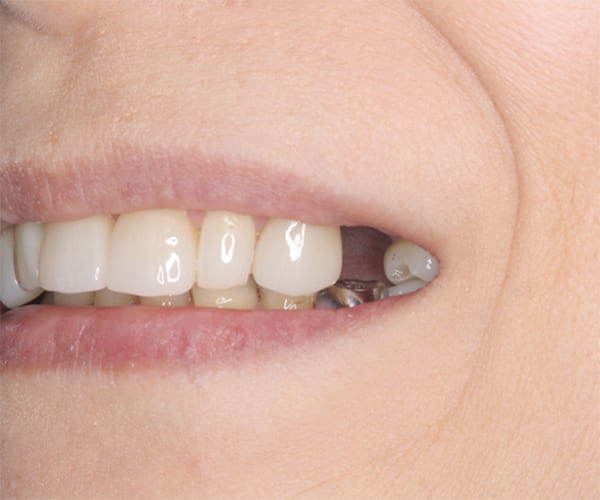

治療前後の口元の比較

こちらは、口を少し開いた時の治療前と治療後の

口元です。

正面から見た時にクラスプが目立たないように、

歯ぐきになじむ素材にて入れ歯を製作し、痛くなく自然に馴染み快適に生活を送れるようになりました。